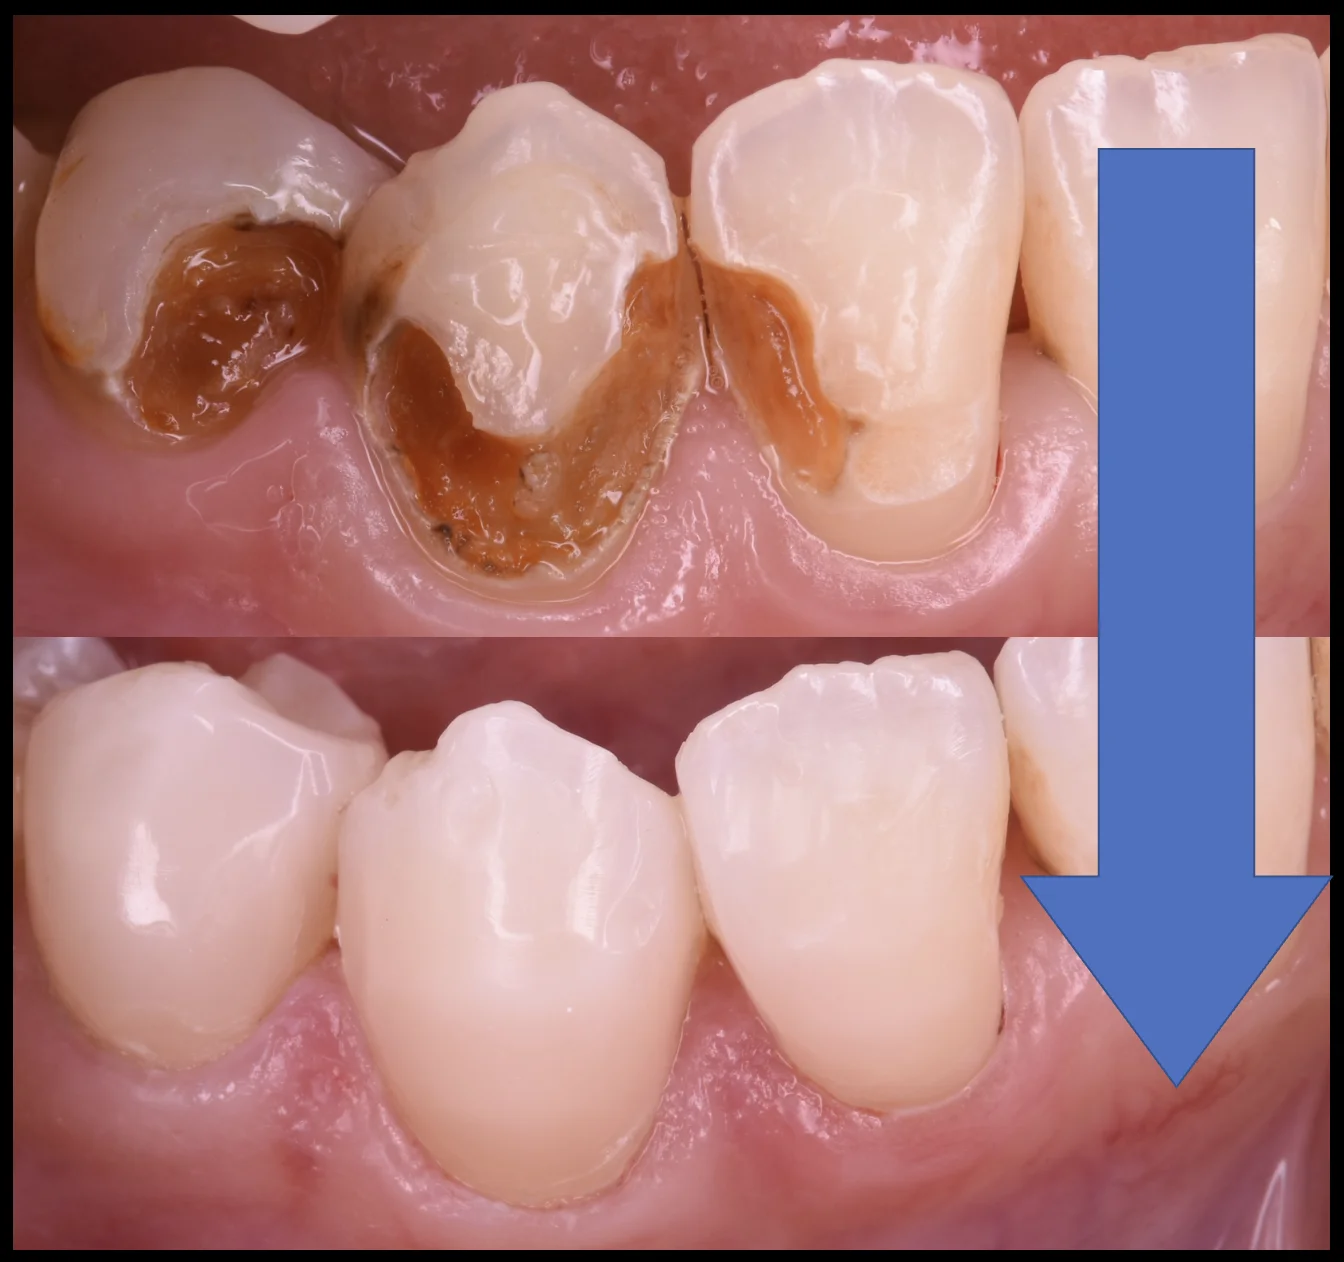

術前術後がこちらになります。

歯の着色部分が消えたため、全体の色も白くなったように見えますね。

長時間の通院+治療お疲れ様でした!

なるべく長持ちするといいですね!